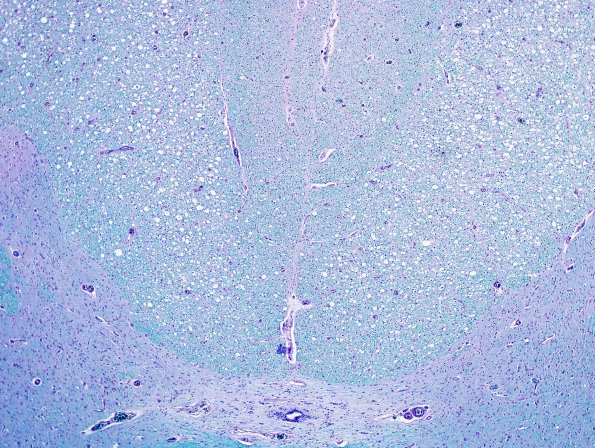

Washington University Experience | INFECTION | Viruses | HIV | HIV - Vacuolar Myelopathy | 1A5 HIV, vacuolar myelopathy (Case 1) LFB-PAS 4X A

Low magnification (4X) image of the dorsal columns showing greater vacuolar involvement of the cuneate fasciculi with relative sparing of the gracile fasciculi (LFB-PAS)